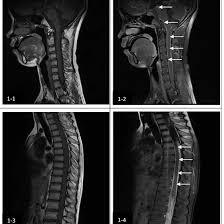

Why is MRI Crucial for Diagnosing Medulla Plain Conditions?

Magnetic Resonance Imaging is important for conditions involving medulla oblongata as it does help in providing the brain’s image by detecting this region and identifying the abnormalities of the region. Here’s why MRI is essential for diagnosing medulla oblongata conditions:

The medulla oblongata is connected at the base of the brain and just below the pons. This area can be easily visualized with MRI since it provides a very detailed image and differentiation from surrounding structures in case there is any structural problem that is easily made.

- Detection of Stroke

Ischemic strokes are hemorrhagic strokes in the medulla oblongata that may lead to worst neurological complications. MRI is the most effective imaging modality to do both types of stroke because it will demonstrate viable parenchyma that has suffered from inadequate blood flow or hemorrhage.

- Tumors and Lesions

Benign or malignant tumours, cysts or any other growths can however arise on or near the medulla oblongata. MRI offer detailed images and we use it to determine the size, location and possible impacts on neighboring structures such as;the brainstem or even the spinal cord.

How MRI Works for Medulla Plain Imaging

MRI is a type of imaging that uses strong magnets and radio waves to get clear images on internal structures for example medulla oblongata. Here’s a breakdown of how MRI works to image the medulla oblongata and other brain structures: